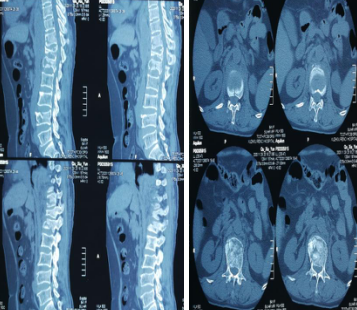

64岁的陈奶奶,因从楼梯上摔下而腰背部剧烈疼痛,活动受限,前来betway在线登陆脊柱科就诊,脊柱科孟磊副主任医师诊断患者为多发胸腰椎骨折(T11-L1、L4),骨块后移继发性椎管狭窄,脊髓圆锥损伤,必须尽快手术治疗。

患者高处坠落,导致多发胸腰椎骨折